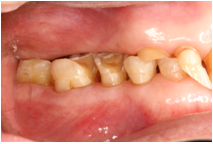

3、牙齿磨耗

牙齿磨耗的原因有很多,包括生理性磨耗,不良咀嚼习惯比如吃硬食;还有由于牙釉质、牙本质发育不良导致的牙齿不正常磨耗。这种磨耗会导致牙本质敏感,牙齿酸痛等情况,久而久之甚至会影响颞下颌关节的健康。有时候牙齿的不均匀磨耗会导致牙齿边缘锐利,刺激口腔黏膜;牙齿的不均匀磨耗也会增加镶牙的难度。牙齿磨耗的治疗策略是避免咀嚼硬食,若是因为氟斑牙或者四环素牙等导致牙釉质发育不好的,则请尽快就诊。

所谓楔状缺损是指牙齿靠近牙龈的地方牙齿缺损。楔状缺损大的时候会导致牙齿敏感、牙齿折断等情况,有时候也会影响后续的镶牙。导致楔状缺损最常见的原因是不正常的刷牙方式。楔状缺损的防治策略是养成正常的刷牙方式,并到治疗科室进行治疗。